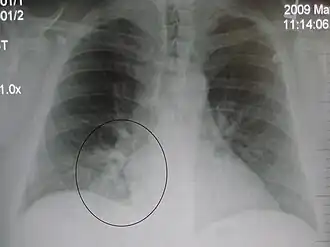

AP CXR showing left lower lobe pneumonia associated with a small left sided pleural effusion -

AP CXR showing right lower lobe pneumonia -